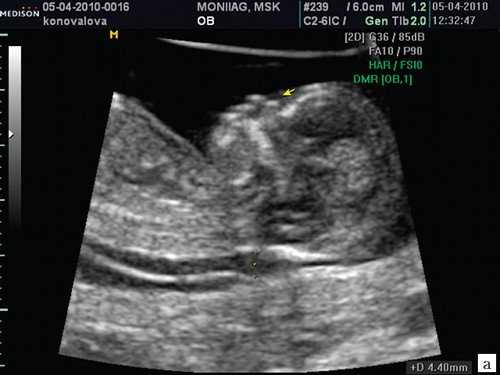

Картина пренатального УЗИ в 35 недель гестации: форма головы аномальная (клубникообразная). Кости при надавливании датчиком не деформируются. Расширение боковых желудочков, передние рога до 10 мм справа и слева. Полость прозрачной перегородки до 9,9 мм. Задние рога - 11 мм, слева - 12 мм. Отмечено расширение IVжелудочка до 12 мм. Имеется гипоплазия червя мозжечка, расширение большой цистерны до 12 мм.

Картина нейросонографии в первые сутки жизни: в задней черепной ямке при коронарных и сагиттальном сканированиях наблюдается крупное анэхогенное («кистовидное») образование, включающее расширенные III и IV желудочек; полушария мозжечка резко уменьшены, червь не определяется; мозжечковый намет смещен вверх.

В динамике по данным НСГ выявлена перивентрикулярная ишемия, подтверждён синдром Денди-Уокера, вентрикуломегалия (как часть симптомокомплекса) и повышенная резистентность сосудов мозга.